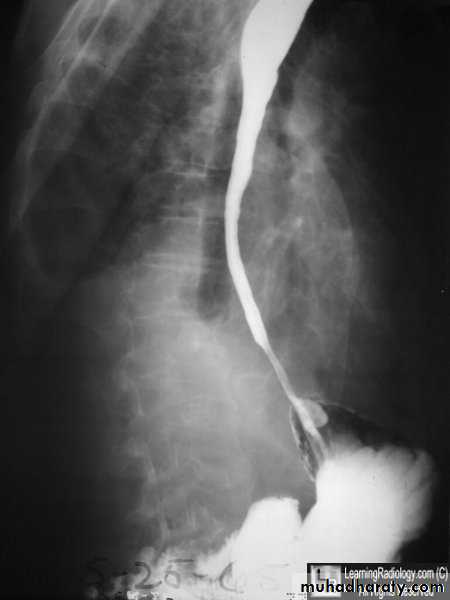

Dilatation

CausesEsophageal atresia

Types:• isolated atresia 8%

• Proximal fistula with distal atresia 1%

• Proximal atresia with distal fistula 85%

• Double fistula with intervening atresia 1%

• Isolated fistula [H-type] 4%